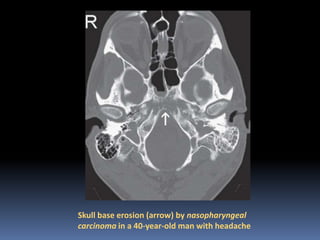

Skull base erosion (arrow) by nasopharyngeal

carcinoma in a 40-year-old man with headache

Skull base erosion(arrow) by nasopharyngeal carcinoma in a 40-year-old man with headache